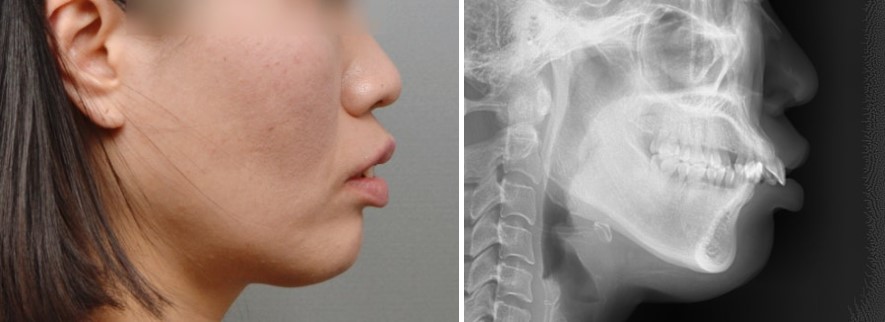

이번 증례는 돌출입과 웃을 때 잇몸이 많이 보이는 거미스마일이 고민이었던 43세 여성 환자분입니다.

엑스레이 상으로는 위 앞니가 윗입술 아래로 많이 내려와 있는 모습이 관찰되었고, 위 앞니가 앞으로 뻐드러진 각도 역시 개선이 필요한 상태였습니다.

입술을 편안하게 다물기 어려운 상태였고, 아래 앞니는 위쪽으로 솟구쳐 깊은 교합을 만드는 데 큰 역할을 하고 있었습니다.

웃는 모습을 보면 잇몸 노출이 많고, 위 앞니의 치아 형태도 가로·세로 비율상 정사각형에 가까워 더 짧아 보이는 인상을 주고 있었습니다.

돌출된 느낌도 줄어들어 옆모습에서도 입술이 보다 조화로운 위치로 이동하였습니다. 환자분 역시 치료 전 가장 큰 고민이던 돌출입과 잇몸웃음이 함께 개선되어 만족도가 매우 높았습니다.

엑스레이 상에서도 치료 전후를 비교하면, 위 앞니의 높이와 각도가 모두 정상 범위에 가깝게 개선된 것을 확인할 수 있습니다.